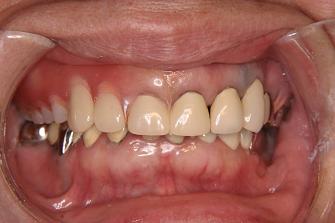

3.

バネなし入れ歯を入れた

状態です!!

* 金属のバネがないので

見栄えが良いです!

入れ歯が入っているとは

気がつかれにくいです!!